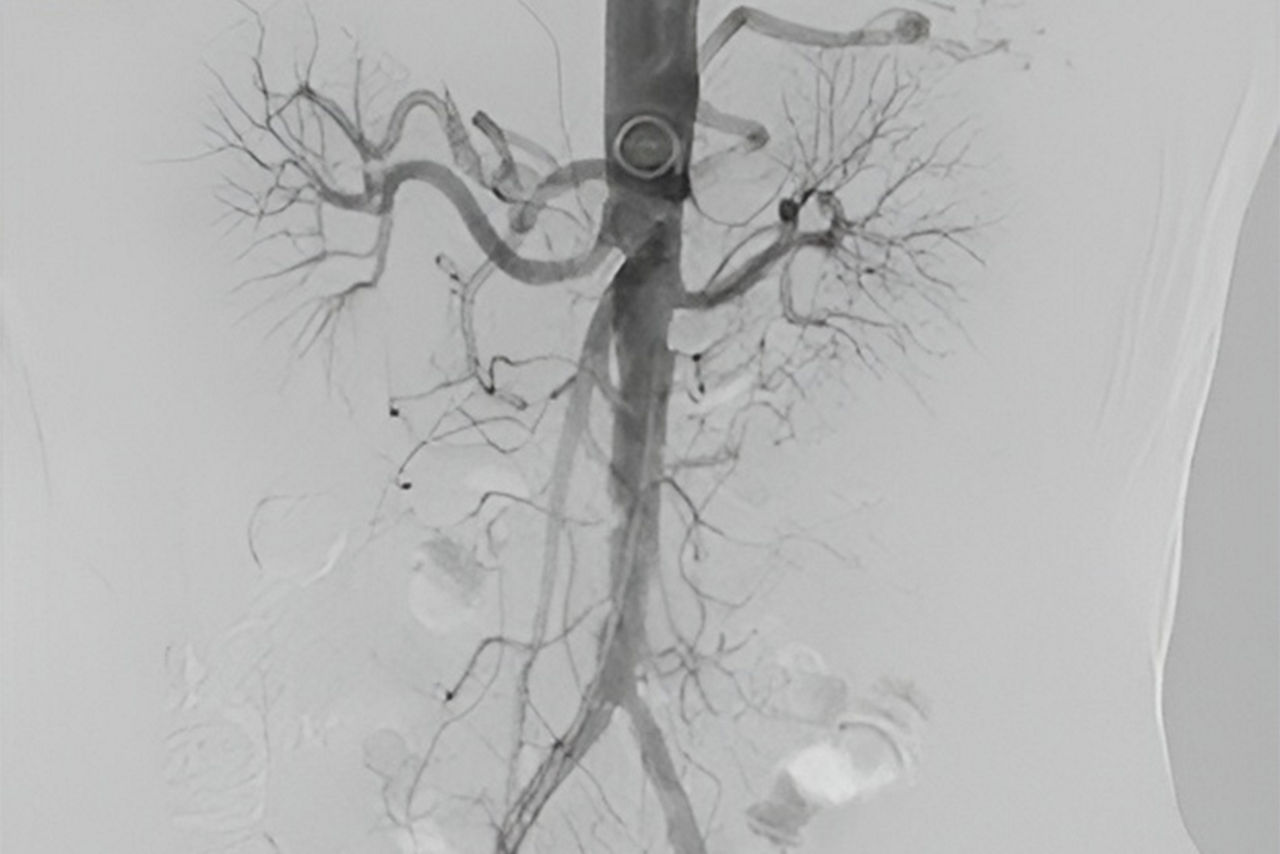

Vessel assist for peripheral

Vessel ASSIST delivers accurate and easy anatomy segmentation and accurate vessel quantification from 3D volumes. It also offers advanced 3D roadmap and augmented image guidance capabilities to guide catheter with confidence.

Use DSA images on larger Field Of View to image the entire anatomy of interest.